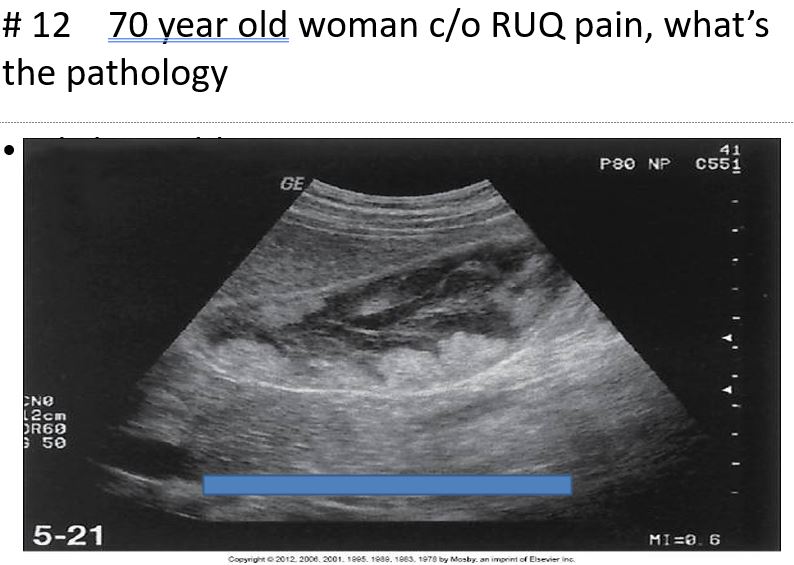

rare and is nearly always a rapidly progressive disease, with a mortality rate approaching 100%.

associated with cholelithiasis in about 80% to 90% of cases

It is twice as common as cancer of the bile ducts and occurs most frequently in women 60 and older

the most common sonographic appearance of the soft tissue mass is a heterogeneous solid or semisolid echo texture.

Gallbladder Carcinoma

The most common primary malignancy of the gallbladder is

Adenocarcinoma